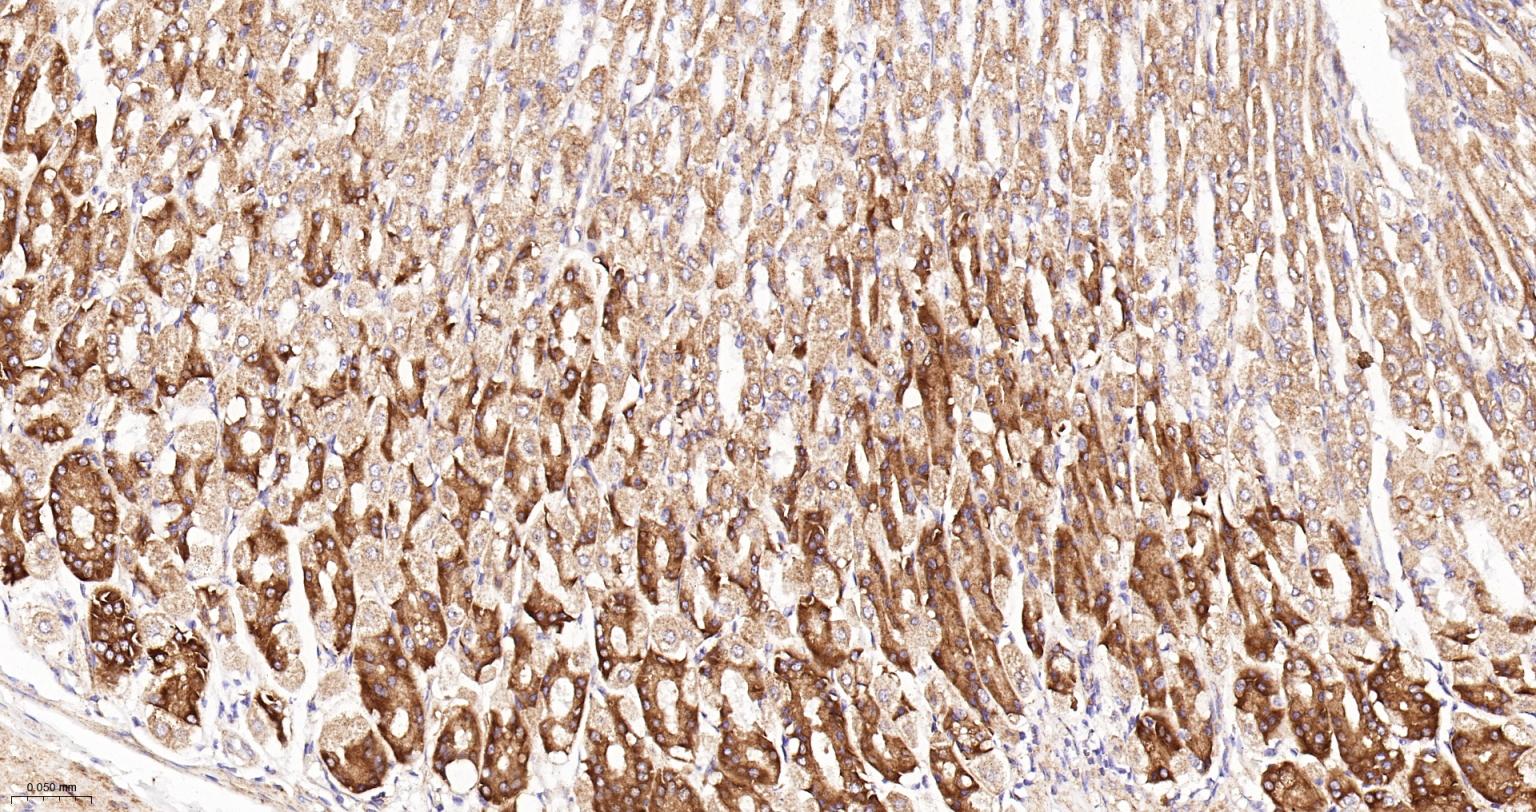

Paraformaldehyde-fixed, paraffin embedded Human Kidney; Antigen retrieval by boiling in sodium citrate buffer (pH6.0) for 15 min; The section was incubated with NDUFS4 Recombinant Monoclonal Antibody, Unconjugated (bsm-62919R) at 1:200 overnight at 4°C, followed by conjugation to the bs-0295G-HRP and DAB (C-0010) staining.